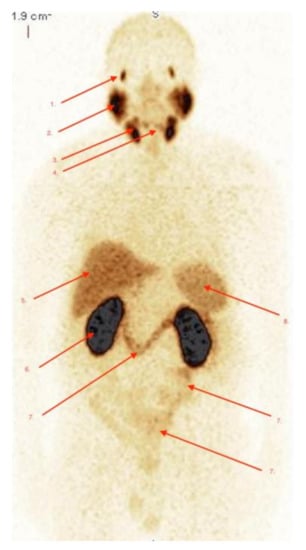

2.2. Biodistribution of Radiopharmaceutical

2.3. Imaging Studies